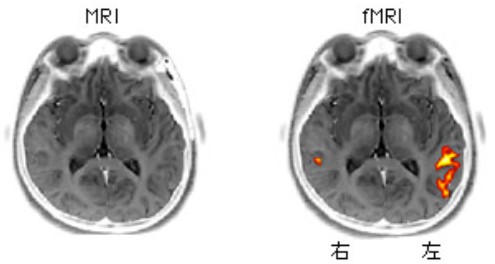

(図5)MRIとfMRI

MRIが構造を写す画像法であるのに対し、fMRIはその時点で機能している脳の部位をも写しだす画像法である。この例では「言語の理解野」が写し出されている。